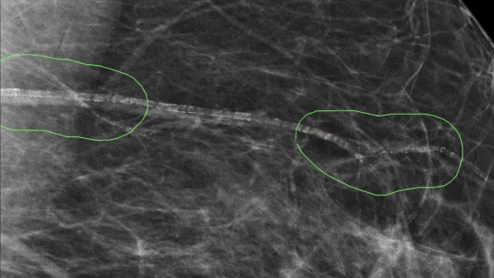

Hospital for Special Surgery pediatric MRI

The conclusions are based on an analysis of safety data from five leading pediatric hospitals, spanning 2017 to 2022, published in JACR